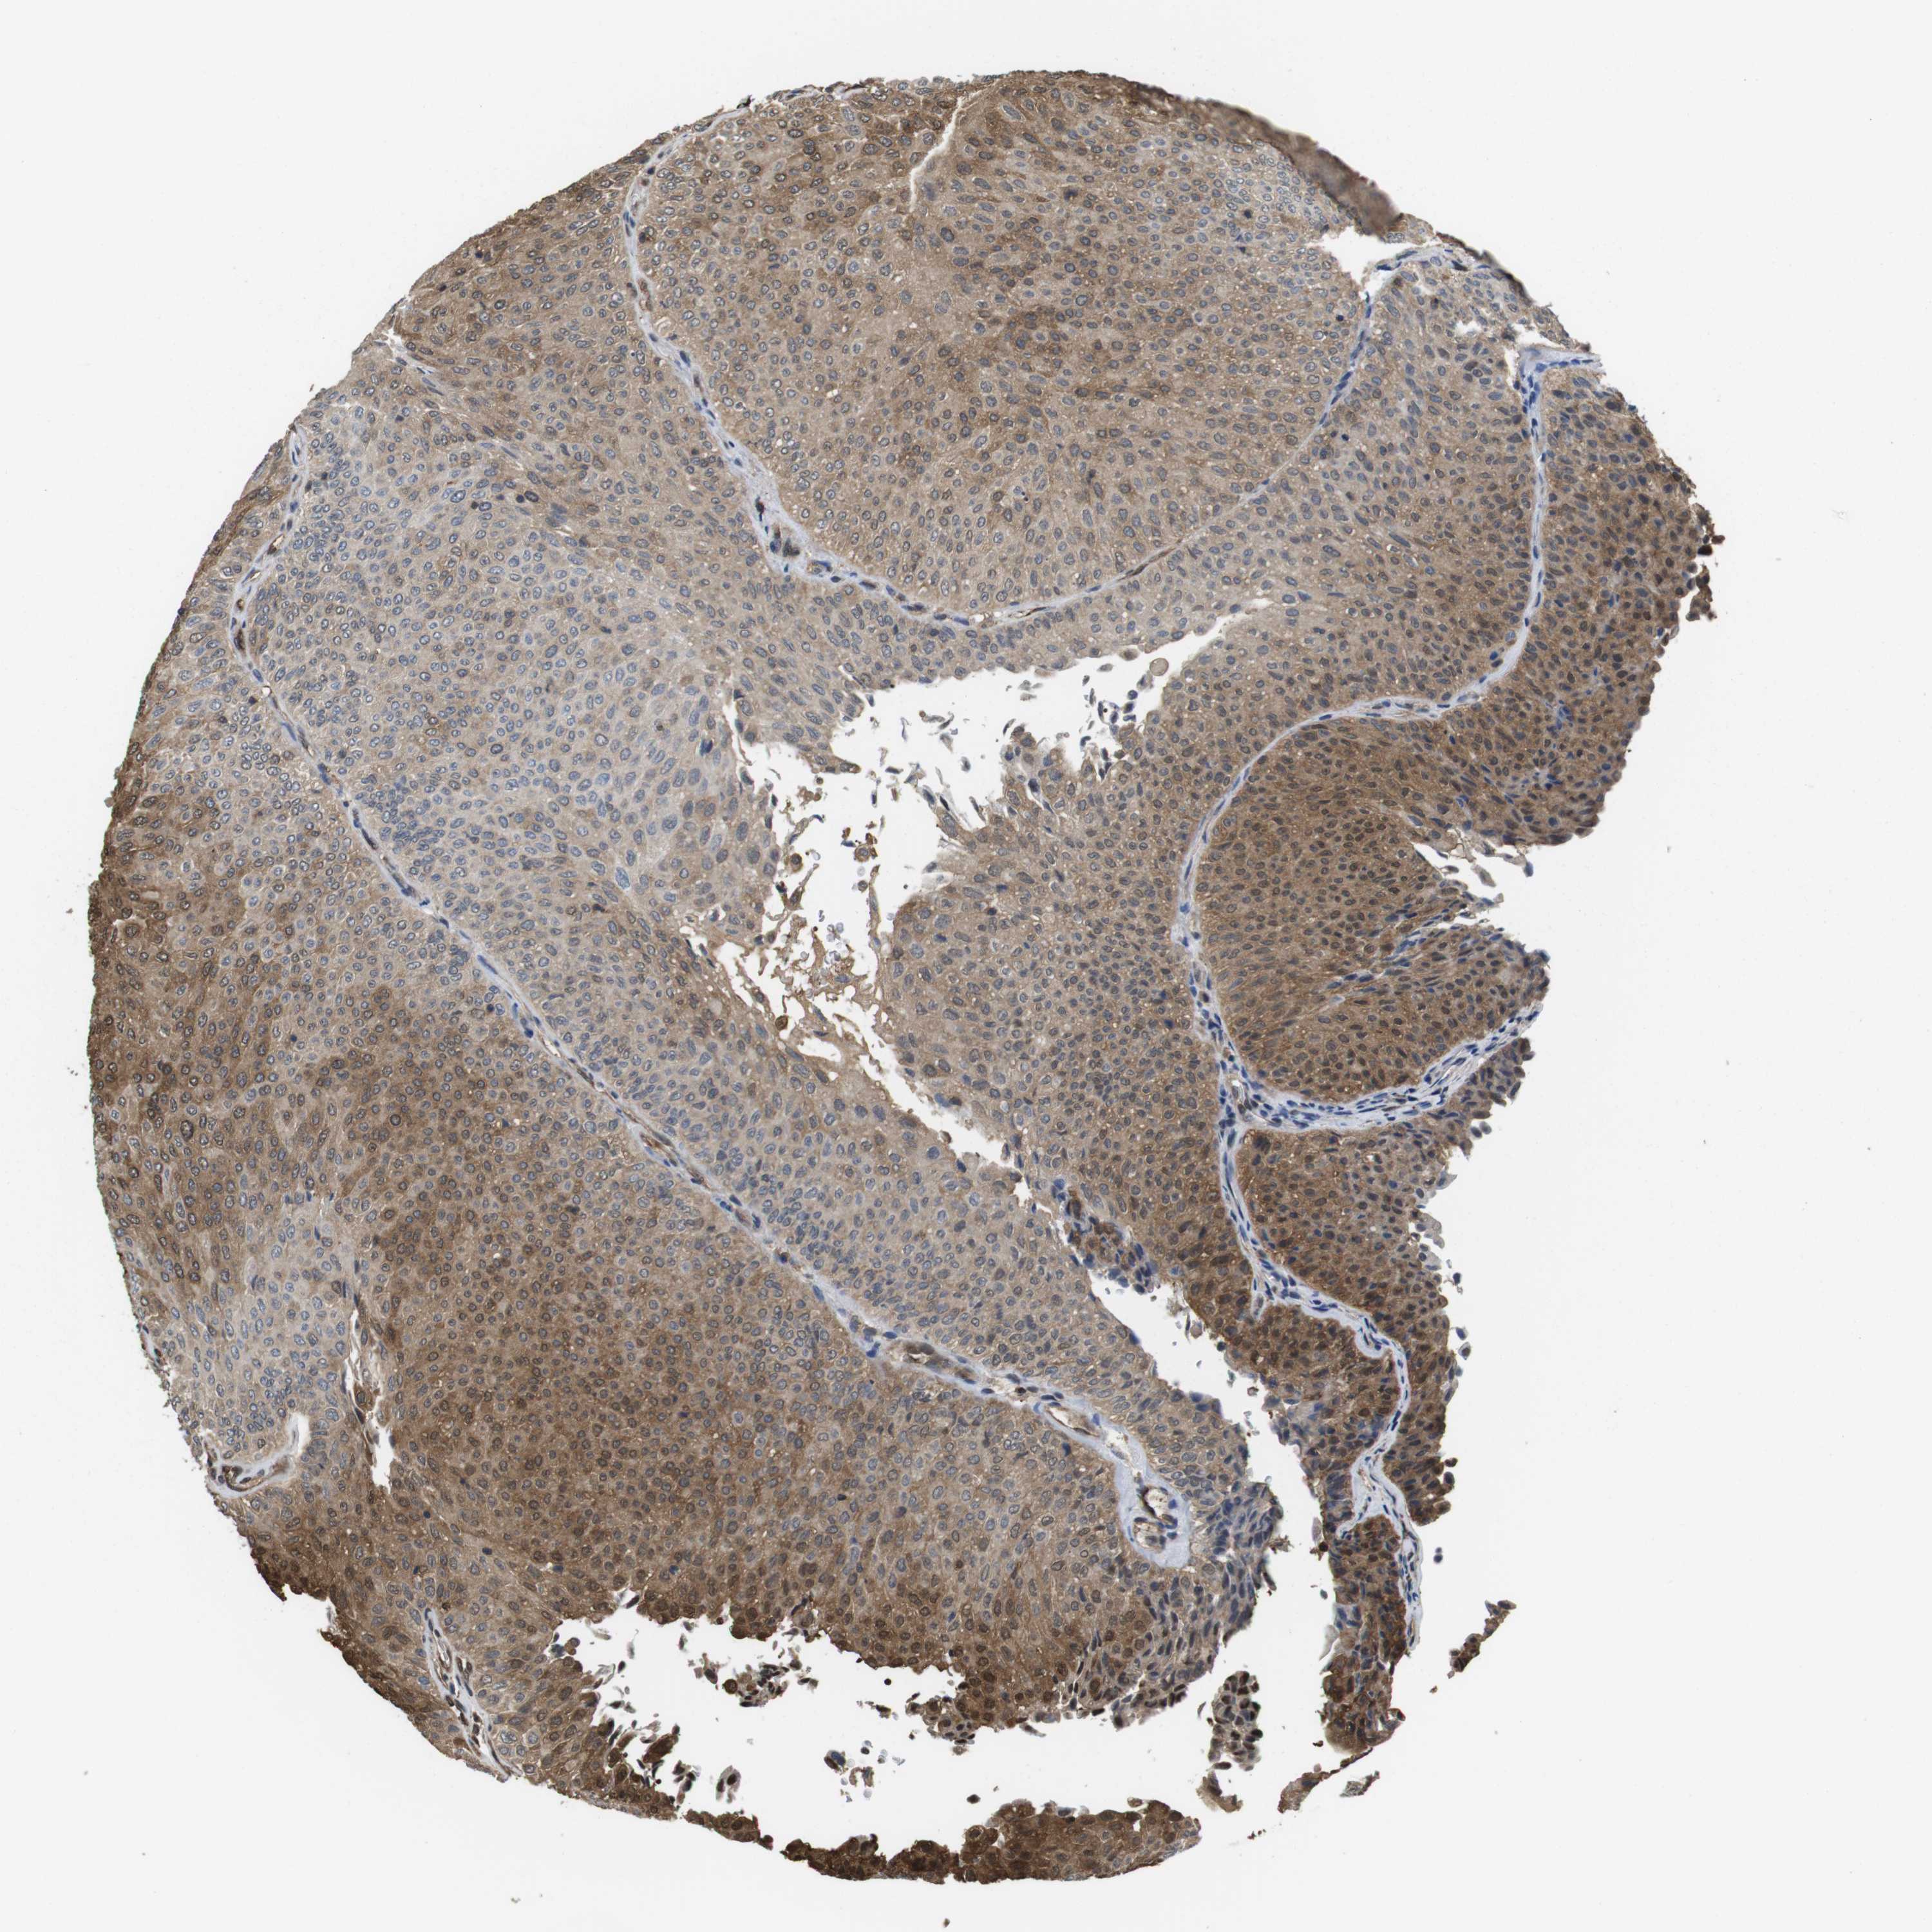

UROTHELIAL CANCER - Protein expressioni

A mouse-over function shows sample information and annotation data. Click on an image to view it in a full screen mode. Samples can be filtered based on level of antibody staining by selecting one or several of the following categories: high, medium, low and not detected. The assay and annotation is described here.

Note that samples used for immunohistochemistry by the Human Protein Atlas do not correspond to samples in the TCGA dataset.

Antibody stainingi

Antibody staining in the annotated cell types in the current human tissue is reported as not detected, low, medium, or high, based on conventional immunohistochemistry profiling in selected tissues. This score is based on the combination of the staining intensity and fraction of stained cells.

Each image is clickable and will lead to virtual microscopy that enables deeper exploration of all samples and also displays staining intensity scores, fraction scores and subcellular localization as well as patient and tissue information for each sample.

Antibody CAB015336

Antibody CAB069404

Staining

High

Medium

Low

Not detected

Intensity

Strong

Moderate

Weak

Negative

Quantity

>75%

75%-25%

<25%

None

Location

Nuclear

Cytoplasmic/membranous

Cytoplasmic/membranous,nuclear

Urothelial carcinoma, High grade